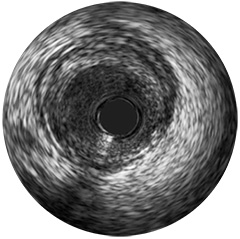

Digital IVUS imaging

imaging

imaging

imaging

Orientación IVUS

es "definitivamente beneficiosa" para los pacientes, y dio lugar a un cambio de los planes de tratamiento el 74% de las veces 1,6,7